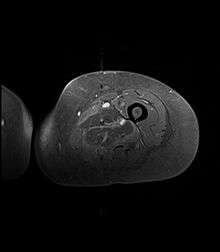

Axial fat suppressed T2 weighted MRI image showing hyperintense signal and enlargement of the left thigh adductor muscle group in diabetic myonecrosis.